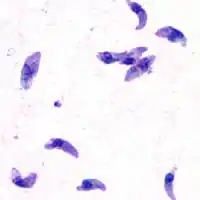

| Giemsa stained T. gondii tachyzoites, 1000× magnification | |

Motile, and quickly multiplying, tachyzoites are responsible for expanding the population of the parasite in the host.[29][30]: 19

When a host consumes a tissue cyst (containing bradyzoites) or an oocyst (containing sporozoites), the bradyzoites or sporozoites stage-convert into tachyzoites upon infecting the intestinal epithelium of the host.[30]: 359 During the initial acute period of infection, tachyzoites spread throughout the body via the blood stream.[30]: 39–40

During the later, latent (chronic) stages of infection, tachyzoites stage-convert to bradyzoites to form tissue cysts.